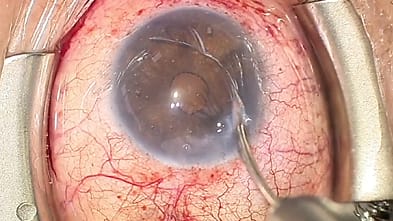

Glaucoma Group Therapy Video: Complications in Canaloplasty